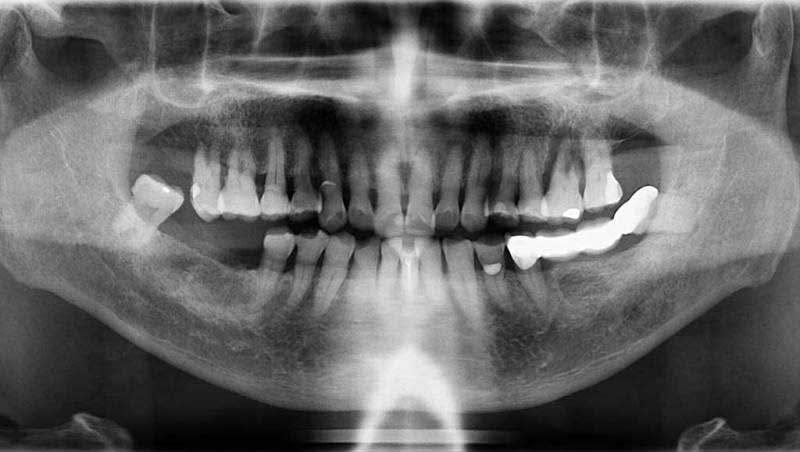

案例3